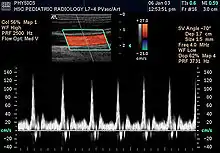

يمكن تحسين صورة الأمواج باستخدام تأثيرات الدوبلر والذي يستعمل لدراسة جريان الدم بالأوعية الدموية، لذلك فاستخدامه مفيد في الدراسات القلبية الوعائية.

تكون الصورة عادةً ملونة، فيظهر الدم اما بلون أحمر أوأزرق حسب اتجاه الجريان بالنسبة للمجس الفاحص. ويقدم الجهاز معلومات ممتازة في تقييم صمامات القلب وارتفاع الضغوط الدموية في الأوعية الدموية.

تحليل لسرعة جريان الدم بالأوعية.